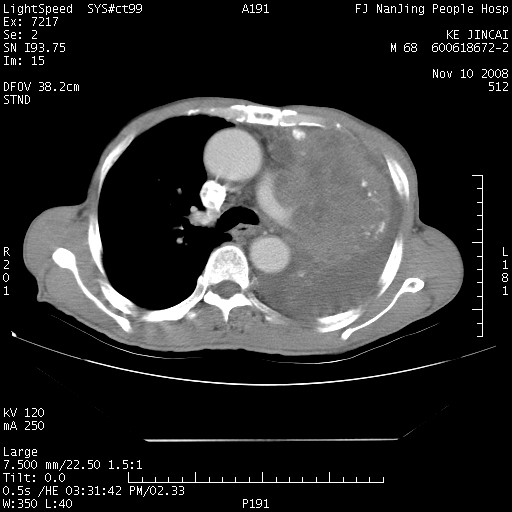

是个很有看头的病例,咋人气那么不旺?没多少人兴趣呢?这个病例几大怪:1   恶性肿瘤侵犯心肌左房怪,心肌一般不会被恶性肿瘤侵犯吧?2   左下肺均匀实变怪,内无含气,有别一般不张实变,含气肺泡完全为液体取代,而非一般不张实变的肺萎陷,冷不丁还以为是肿大的脾脏3   肿瘤本身怪,像tb肺不张4   这么有看头的病例没人气怪。呵呵。

左肺恶性肿瘤侵犯肺动脉,左心房内瘤栓,胸膜转移。